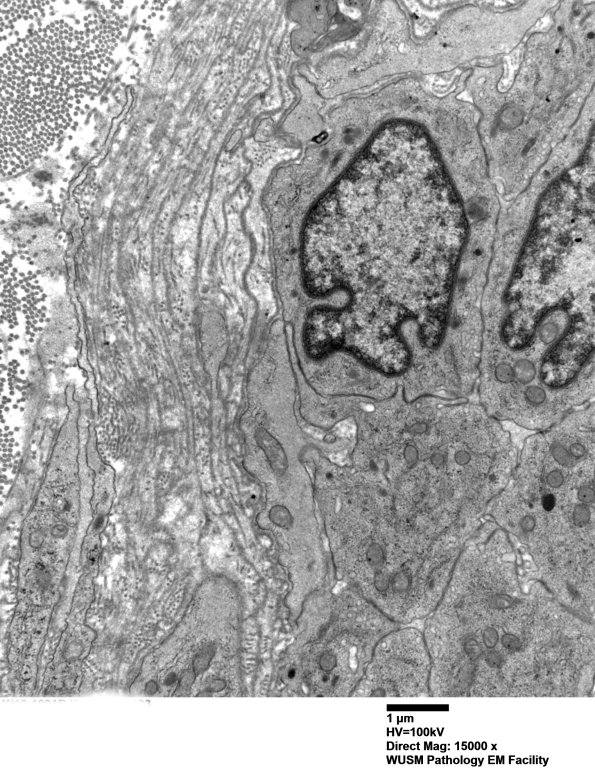

In this case the expanded wall is composed largely of basal membranes. (electron micrographs)